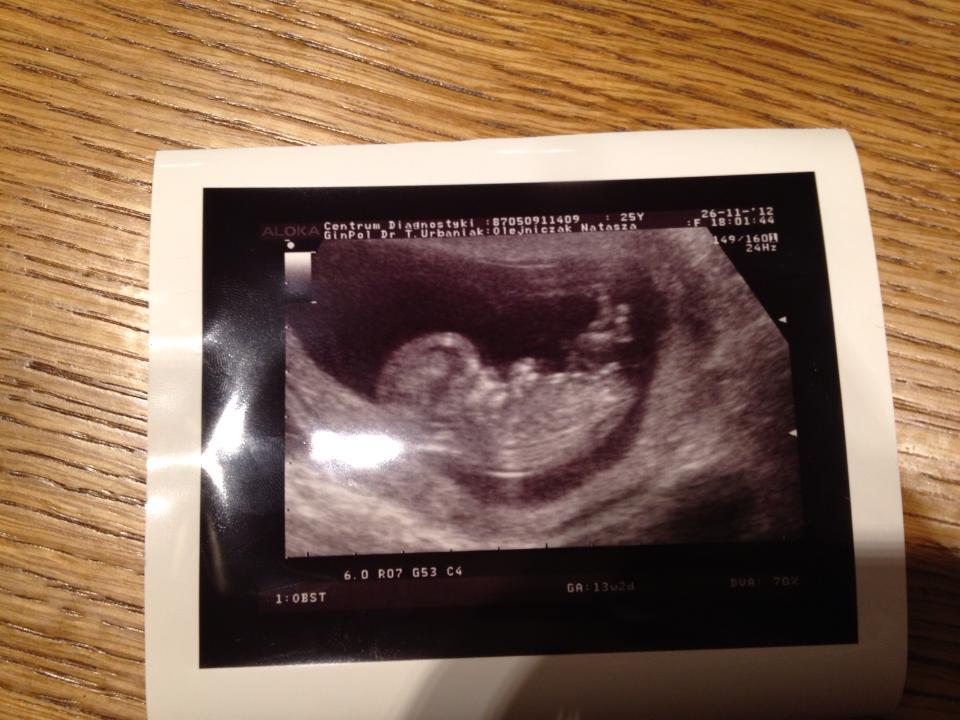

Pokusiłam się na badania prenatalne. Nie było zastrzeżeń co do przebiegu ciąży ani niczego niepokojącego, ale skoro mogło mnie coś uspokoić i wywalić z głowy głupie myśli- jestem na tak!

Okruch oczywiście cały, zdrowy. Wszystko takie jak być powinno, od kości po krew i inne cuda. Serduszko bije mocno i głośno. A samo Dziecie w brzuchu szalało jak na najlepszej imprezie! Do góry, na bok, przodem, tyłem...ale oczywiście to co mnie ( prócz zdrowia) interesowało najbardziej to się już nie dowiedziałam. Płeć Zośki ( dziwnie to brzmi... ) nadal jest tajemnicą chociaż jak to lekarz na koniec stwierdził " jest bardzo duże prawdopodobieństwo, że to jednak Zośka".. no i masz. Czyżbym się myliła co do zawartości brzucha?